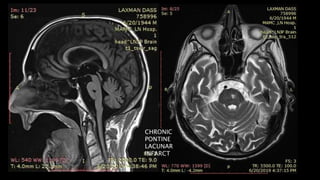

Chronic Lacunar Infarcts

CHRONIC

PONTINE

LACUNAR

INFARCT

• #123 C/o 75 y old men showing T1 hypointense and T2 hyperintense foci in mid pons

• #124 Showing signal suppression on FLAIR image with no enhancement on post contrast scan s/o chroniclacunar infarct. Also there are T2/FLAIR hyperintensities in subcortical and periventricular white matter b/l s/o ischemic demylination and glioenchephalomalcic changes in right parietal refgion

• #125 This is the another c/o CHRONIC LACUNAR infarct in right basal ganglia appearing hypointense on T1/ hyper on T2 with signal suppression on FLAIR